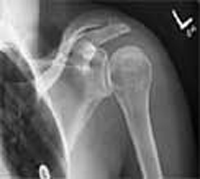

Inflamación del hombro

La inflamación del hombro es un dolor provocado por la excesiva fricción o contracción del manguito rotador y el omóplato.

Esta alteración suele presentarse en personas que realizan movimientos repetitivos del brazo y el hombro. La causa de esta inflamación puede ser: